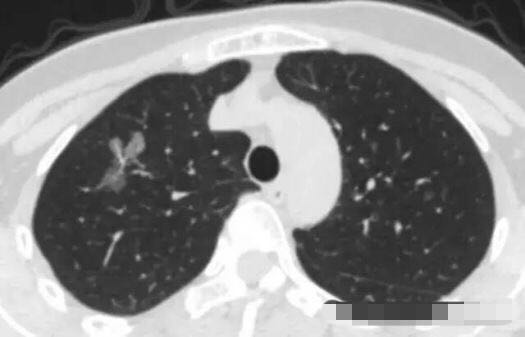

病例1 .

2014年 首次发现右肺上叶GGO,病灶直径8.3毫米, 2016年复查发现右肺上叶GGO,病灶直径12.4毫米。2年大约生长4毫米,平均1年生长2毫米。2016年手术病理结果:浸润性腺癌。

2014年 病灶8.3毫米

2016年病灶直径12.4毫米